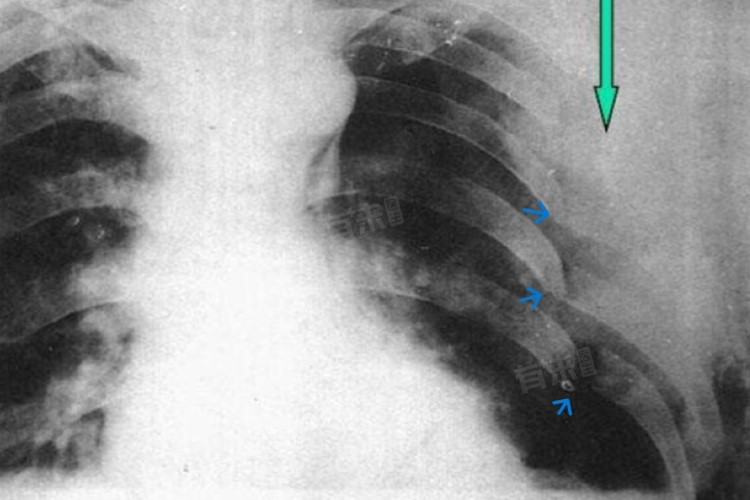

3、严重肋骨骨折:患者大多疼痛剧烈,可能伴有呼吸困难、胸闷等症状,骨折处可能有明显的畸形或错位,活动严重受限。严重肋骨骨折往往需要更长的时间来恢复,可能需要6周以上甚至数月,在骨折未完全愈合之前绝对不可以同房,以免加重骨折或引起其他并发症。